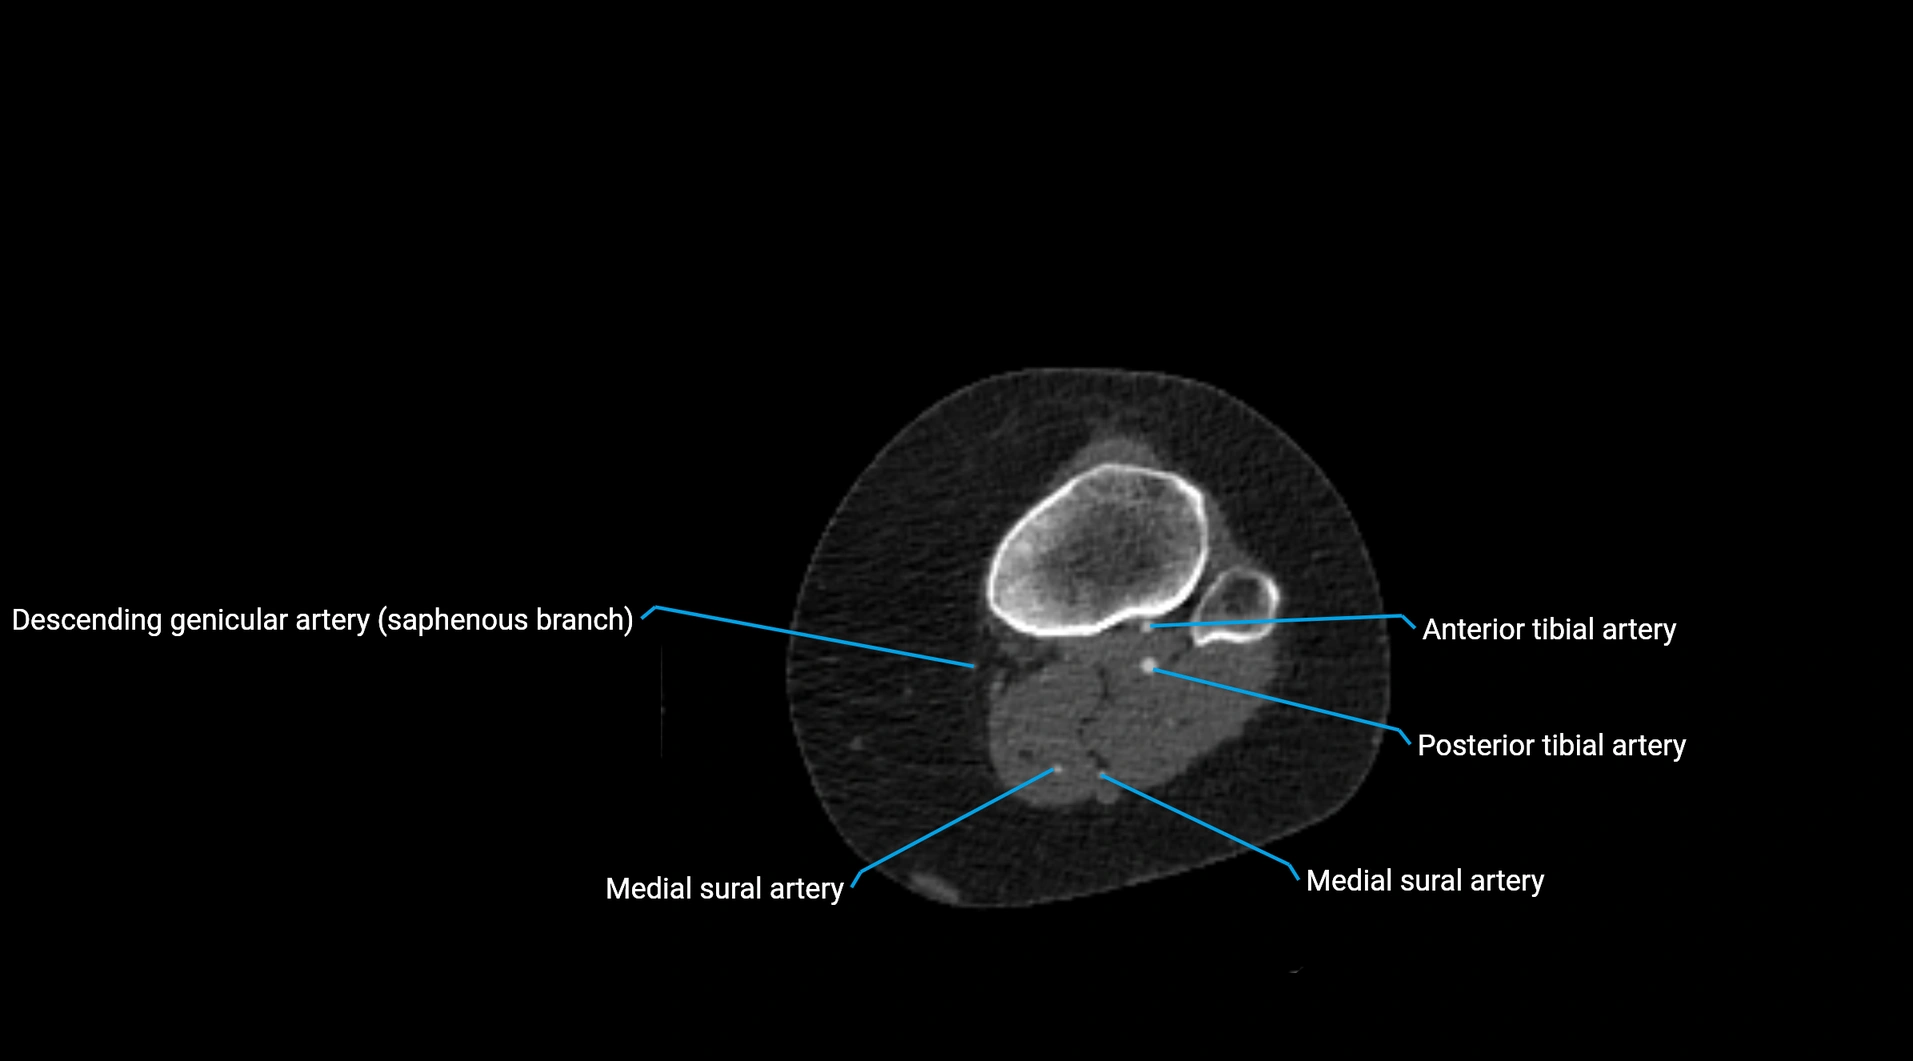

CT images

image